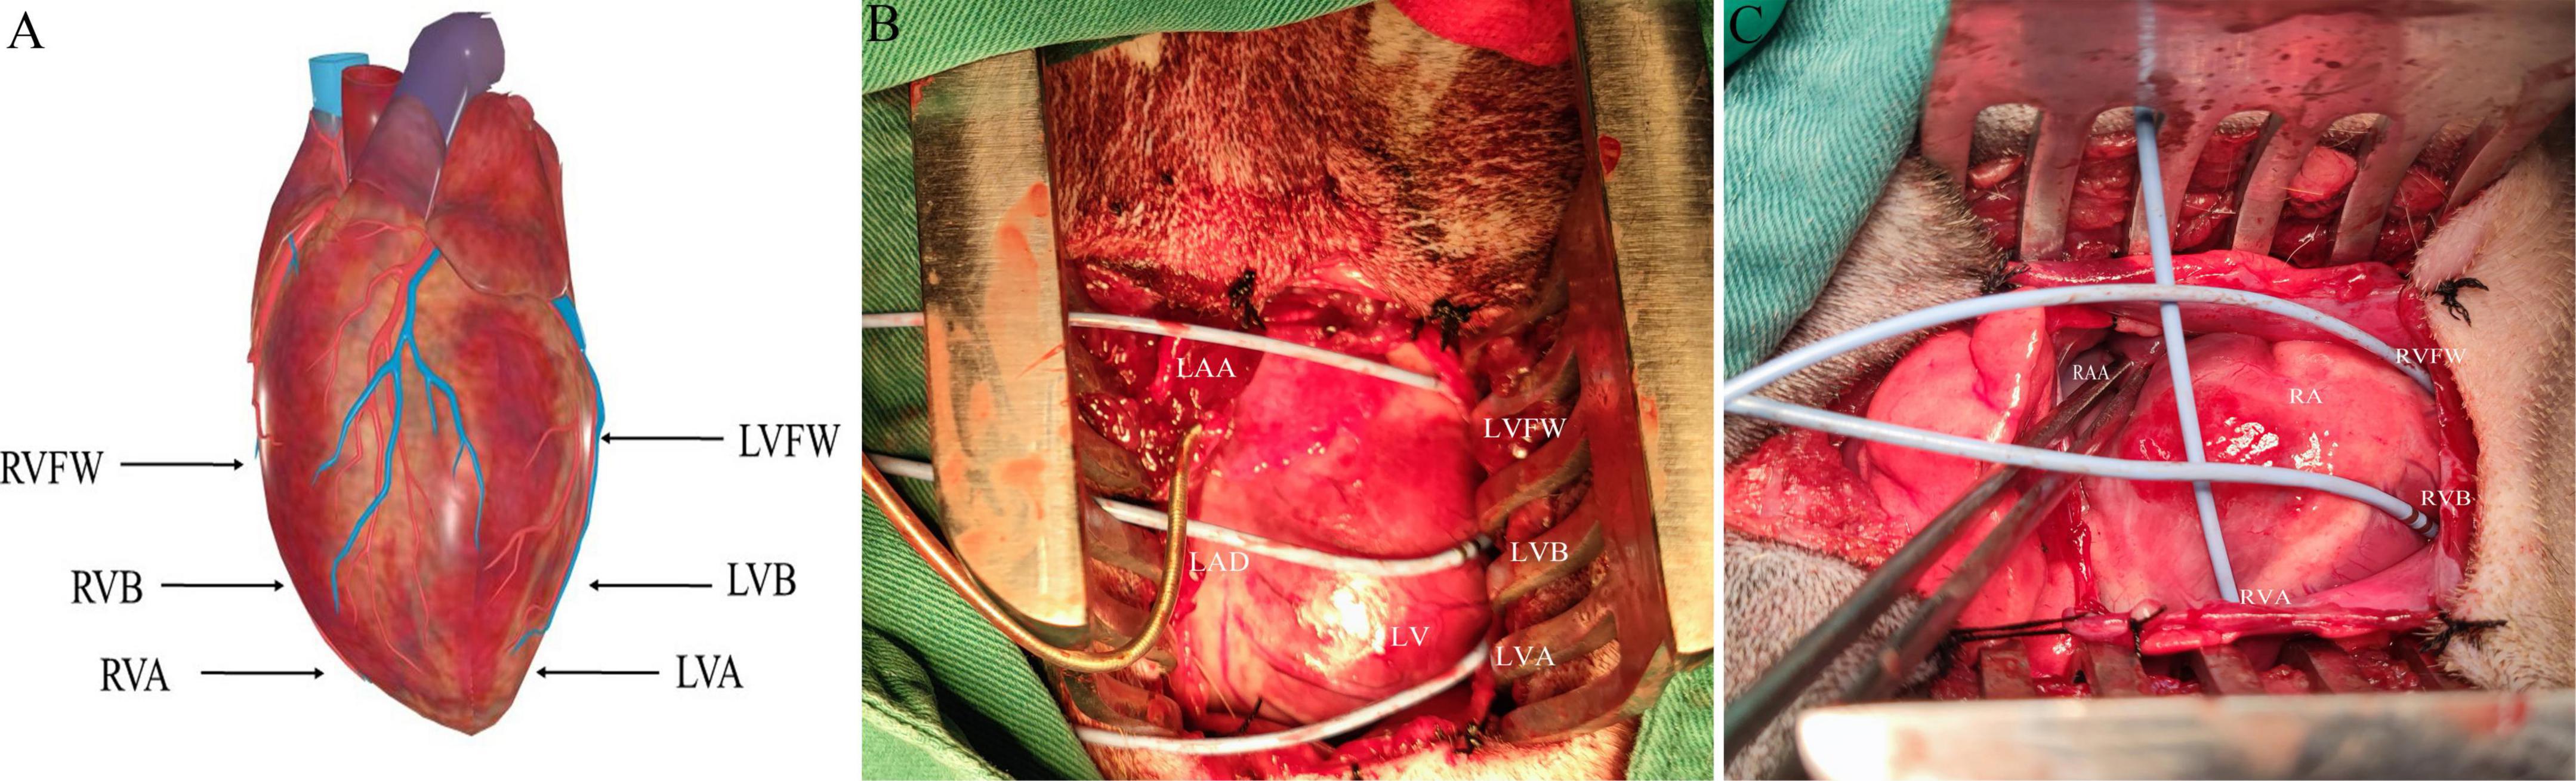

The electrophysiological testing was performed before and after MNS. Effective refractory period (ERP) in the right ventricular epicardium at the apex (RVA), free wall (RVFW), and base (RVB) and left ventricular epicardium at the apex (LVA), free wall (LVFW), and base (LVB) were evaluated during ventricular pacing at 300 ms cycle lengths (CLs) using stimuli at twice threshold. Figure 3 shows the schematic diagram of electrode placement position during electrophysiological testing. After every eighth drive stimulus (S1), a premature extra stimulus (S2) was introduced. As the S1–S2 intervals approached the ERP, decrements were reduced to 2 ms. ERP was the most prolonged S1–S2 interval at which S2 failed to capture. ERP dispersion was the maximum difference among all sites tested.

Figure 3. The schematic diagram of electrode placement position during electrophysiological testing (A). (B,C) Are electrodes placed in the left ventricle and right ventricle, respectively. LVFW, left ventricular free wall; LVB, left ventricular base; LVA, left ventricular apex; LAA, left atrial appendage; RVFW, right ventricular free wall; RVB, right ventricular base; RVA, right ventricular apex; RAA, right atrial appendage.